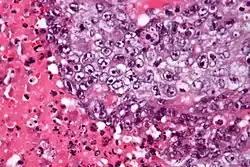

| Micrograph of an embryonal carcinoma showing its typical features – prominent nucleoli, marked nuclear atypia, necrosis, and nuclear overlap. H&E stain. | |

The microscopic features include: indistinct cell borders, mitoses, a variable architecture (tubulopapillary, glandular, solid, embryoid bodies – ball of cells surrounded by empty space on three sides), nuclear overlap, and necrosis.

Solid (55%), glandular (17%), and papillary (11%) are the most common primary patterns (predominant architectural pattern occupying at least 50%). Other less common primary patterns included nested (3%), micropapillary (2%), anastomosing glandular (1%), sieve-like glandular (<1%), pseudopapillary (<1%), and blastocyst-like (<1%).[4]

An important key to distinguish it from other tumors, such as seminoma (vacuolated), teratocarcinoma (three differentiated germ layers), yolk sac tumor (Schiller–Duval bodies), and the Sertoli–Leydig cell tumor (strings of glands), is that the embryonal carcinoma cells are "trying" to evolve into their next stage of development. So in the testicle, they are often observed as blue cells attempting to form primitive tubules.[6]